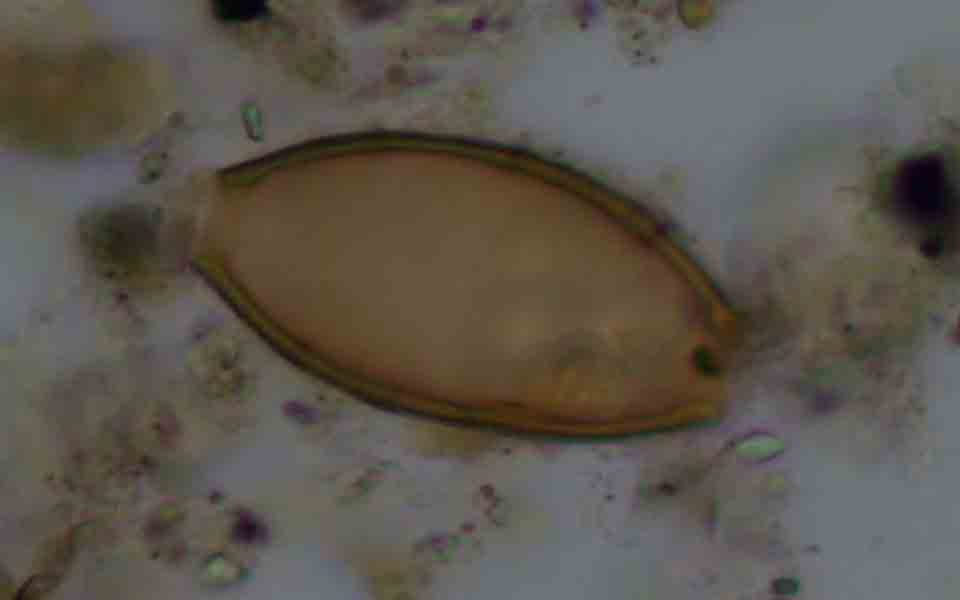

Η μελέτη αποκάλυψε σε τέσσερις από τους 25 σκελετούς (ποσοστό 16%) ότι μέσα στα αρχαία κόπρανα υπήρχαν υπήρχαν αυγά από δύο είδη εντερικών παρασιτικών σκωλήκων (έλμινθες): την ασκαρίδα (Ascaris lumbricoides) μήκους έως 30 εκατοστών και την τριχουρίδα (Trichuris trichiura) μήκους τριών έως πέντε εκατοστών. Το πρώτο παράσιτο βρέθηκε σε δείγματα από την εποχή του Χαλκού και μετά, ενώ το δεύτερο από τη νεολιθική εποχή και μετά.

Τα δύο είδη που εντοπίσθηκαν στην Κέα, είναι παράσιτα, τα οποία εξαπλώνονται συνήθως μετά από μόλυνση των χεριών, των υδάτων ή της τροφής με ανθρώπινα κόπρανα, ιδίως στους αγροτικούς πληθυσμούς με κακές συνθήκες υγιεινής. Και τα δύο παράσιτα, η ασκαρίδα (που προκαλεί τη λοίμωξη ασκαρίαση) και η τριχουρίδα (που προκαλεί την λοίμωξη τριχουρίαση), θεωρούνται ότι έχουν μολύνει τους ανθρώπους από τα βάθη της εξέλιξης, συνεπώς είναι πιθανό να μεταφέρθηκαν στην Κέα από τους πρώτους κατοίκους της.